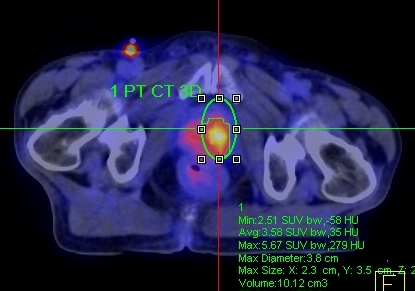

Hình dưới đây cho thấy giá trị của PET/CT trong phát hiện tổn thương tại tuyến tiền liệt.

Hình 1. Bệnh nhân Phan L. Th., nam, 75 tuổi, chẩn đoán: Ung thư tuyến tiền liệt. Trên hình CT, FDG-PET và FDG-PET/CT thấy khối u thùy trái tuyến tiền liệt tăng hấp thu FDG mạnh, max SUV=5,57.